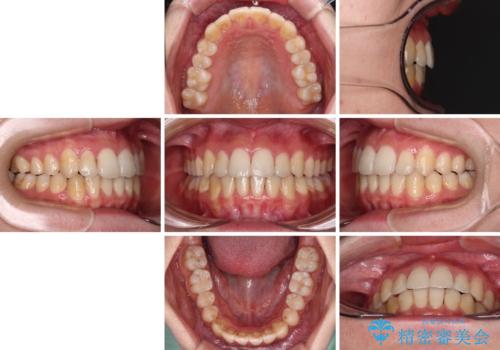

インビザラインで歯列を移動する前に、上顎前歯をワイヤー矯正で整え、その後上下歯列をインビザラインにて矯正治療を行うこととしました。

舌側転位している側切歯特有の、切縁の位置が不揃いであったり、根元が内側に引っ込んだ状態であったりという、インビザライン独特の仕上がりになることなく、きれいに整った歯列とすることができました。